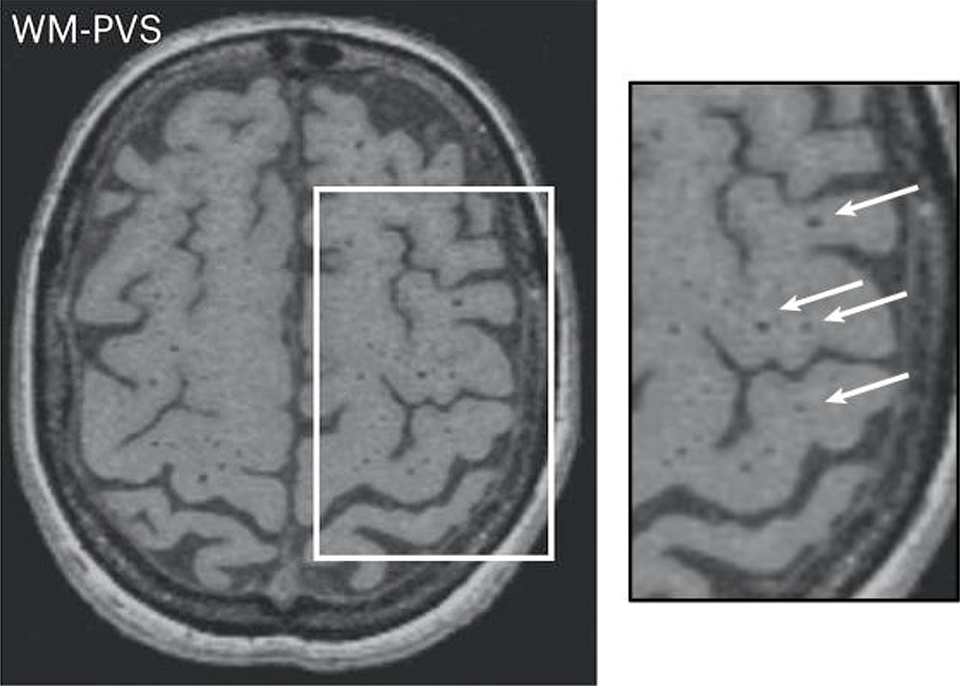

MRI-visible dilated perivascular spaces (dPVS)

BGdPVS (basal ganglia) and WMdPVS (white matter)

note MRI‐visible dilated perivascular spaces in healthy young adults: A twin heritability study - PMC has false positive reduction

In our study, frequency distribution of WM-PVS grades according to different severity levels of ASD shows an increasing trend, with 80% “mild” ASD patients with less than 40 WM-PVS (WM-PVS grade 0–3) in a single MRI section and 53% “severe” ASD patients with more than 40 visible WM-PVS (WM-PVS grade 4). Consistently, patients with ASD and insomnia tend to have higher WM-PVS volume compared to ASD patients without sleep issues, although this result was not statistically significant. Previous studies reported an association between higher PVS visibility on MRI and impaired sleep quality and efficiency (Berezuk et al., 2015; Aribisala et al., 2020) and obstructive sleep apnea (Song et al., 2017). In fact, sleep has been shown to be important for a proper functioning of the glymphatic system (Hablitz and Nedergaard, 2021).